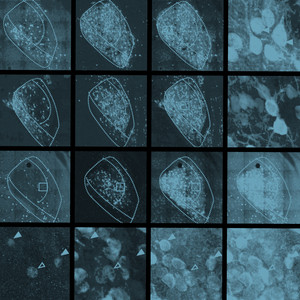

A recent study from our Division of Intramural Research provides new insights into the mechanisms by which the brain influences the perception of pain. This study, which was done in mice, showed that a part of the brain called the central amygdala—which is associated with emotional processes—can act as a “switch” to upgrade or downgrade pain signals.

The “switch” involves two different types of nerve cells. When one type of cell in the amygdala is activated, pain signals increase. When the other type is activated, they decrease.